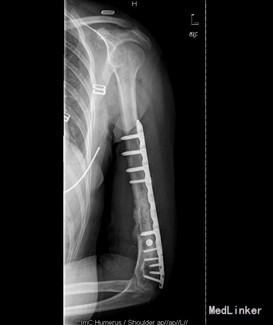

初步诊断:1、左肱骨骨折术后骨不愈合。2、左肩、左肘关节活动障碍 诊疗计划:择期行左肱骨髓内钉取出术、左肱骨骨折钢板螺钉内固定术,人工骨植骨。

术中见肱骨下份原骨折处软组织肿胀,瘢痕形成较多,有少量骨痂生成,能见原骨折端。取出髓内钉及固定钢丝后,骨折明显不稳定有假关节活动。未见明显炎性增生、渗出及坏死组织。并取随内及骨折周围部分组织送病检及培养。